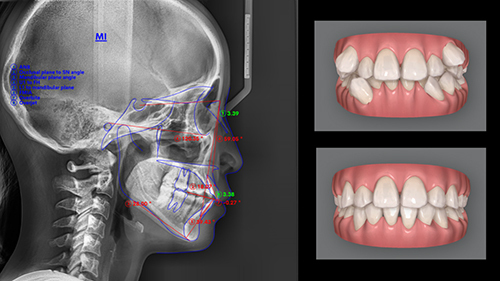

矯正後の歯並びはどうなるんだろう…。本当に理想の口元が手に入るの?そんな不安を抱える方もいらっしゃるかと思います。

当院では、最新の口腔内スキャナーをを使用した歯並びのシミュレーションを無料でご提供しています。

これにより治療中の歯の動きや、矯正後の歯並びをイメージすることが可能です。

インビザライン・ダイヤモンド・プロバイダー・1,600症例のDr.三嶋が歯並びの無料相談を実施中。

治療後の歯並びをシミュレーション動画でお見せします。